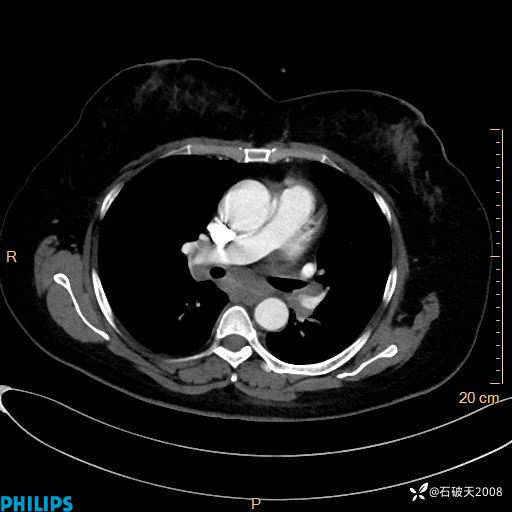

纵隔窗

动脉期